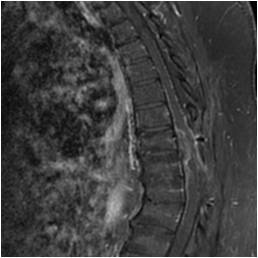

Idiopathic Hypertrophic Pachymeningitis

A chronic progressive diffuse inflammatory fibrosis of the dura mater. Diagnosis of exclusion since meningioma, lymphoma, sarcoid and TBc can present in a similar fashion. MRI findings of low signal intensity mass extending over several levels with linear or nodular peripheral enhancement (representing active inflammation) highly suggestive of the diagnosis. [ Article ]

chronic myelopathy with several decompressions

Courtesy Jay A Kaiser MD